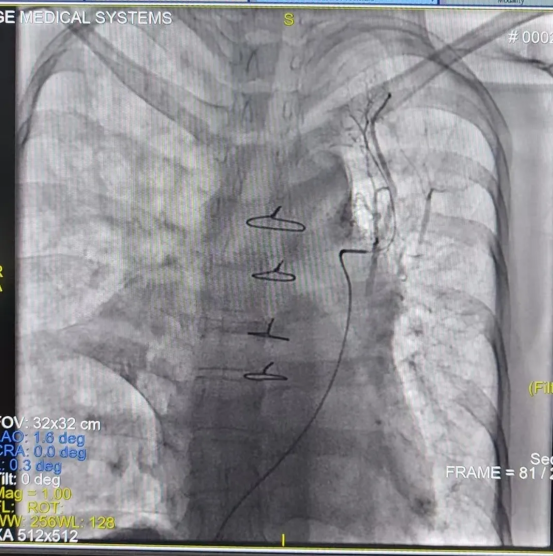

由于该手术难度极高(CMI值达17.8),心内一科与肺血管病与介入医学科联合为其制定周密手术方案。术前肺动静脉增强CT提示左肺动脉狭窄、左上、左下肺静脉闭塞,右上肺静脉狭窄。术中,心内一科尚粉青主任与孙杨医生行右心导管检查,明确其属于“毛细血管前肺动脉高压”。李积安主任、王鹏军副主任医师行经肺动脉间接肺静脉造影,再次证实左上、左下肺静脉闭塞,右上肺静脉狭窄。成功行房间隔穿刺,左肺肺静脉造影发现左上肺静脉完全闭塞,反复导丝尝试后成功开通了闭塞的肺静脉并行球囊扩张及支架植入,后再次行右肺静脉扩张,造影证实肺静脉回流正常,术后患者病情平稳,胸腔积液迅速吸收,症状明显改善,3天后胸腔积液完全消失。9月2日开学之际,李女士康复出院,终于能够回家照顾孩子,重归正常生活。

左上肺静脉支架植入术后